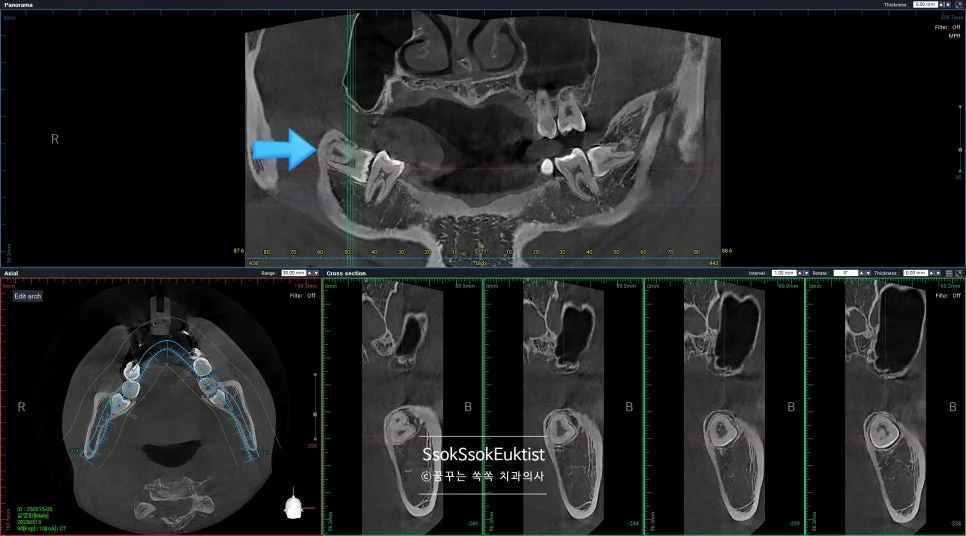

CBCT 3차원 영상 — 사랑니와 신경관의 인접 관계 확인

발치 전 CT를 보면 신경관과 맞닿아 있어 발치 난도가 높은 케이스임을 알 수 있습니다.

CBCT 3차원 영상 — 서로 다른 방향으로 휘어진 복잡한 뿌리

3차원 사진을 통해 보면 뿌리가 서로 다른 방향으로 휘어 있어 뼈를 잡고 있는 모습인데요^^ 이런 뿌리의 사랑니의 경우 한꺼번에 나오지 않으므로 머리를 분리하는 것 외에 뿌리도 분리하여 사랑니를 제거해야 합니다.

그렇기에 매우 어려운 발치 난도이며, 이러한 어려운 발치를 해낸다면 사랑니 발치를 잘하는 치과로 볼 수 있겠죠^^